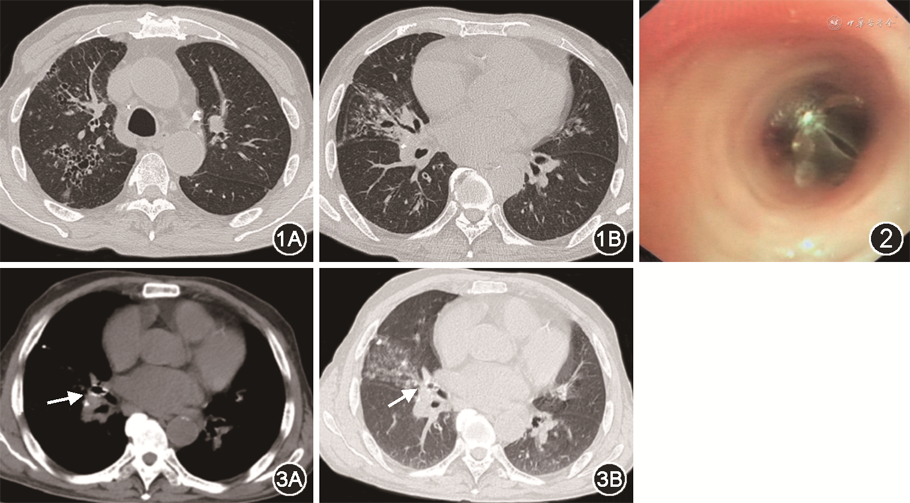

入院体格检查:呼吸20次/min,右肺闻及干啰音,无口唇紫绀,无颈静脉怒张,无杵状指,心肺腹未见其他异常。胸部CT示右肺中叶容量减少和炎性渗出,右中叶支气管扩张症,右上叶支气管轻度扩张症(图1)。由于该患者高龄,右中叶因为反复感染导致的局部粘连而难以实施右中叶切除术,故未行肺叶切除术治疗咯血。于2020年11月18日接受支气管镜介入治疗。静脉麻醉后,使用喉罩为患者供氧。可弯曲支气管镜(Olympus 1T260,日本)经喉罩内腔进入气管和支气管,发现右中间支气管和右中叶支气管内大量血块。清理血块后,见右中叶支气管内少量活动性出血。局部喷洒稀释肾上腺素(1∶10 000)止血后,置入1个型号为5.5的支气管活瓣(Zephyr endobronchial valve,PulmonX Inc.,美国)于右中叶支气管内(图2),支气管出血停止。术后患者未出现并发症,抗感染治疗3 d后出院。术后1个月,复查胸部CT示支气管活瓣在位良好(图3)。随访6个月咯血未复发,未出现并发症。